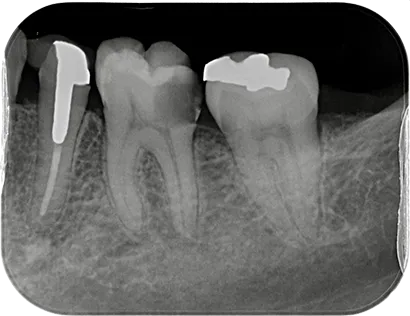

当院の症例を掲載しています。

当院での治療をご検討されている方は是非ご覧ください。

虫歯など様々な理由で歯の内部に細菌感染が広がることがあります。歯内療法(根管治療)とは、文字通り歯の内部の治療で、感染が広がった根管(神経が通る管)に対して適切な治療を行うことにより歯の機能を回復させることができます。